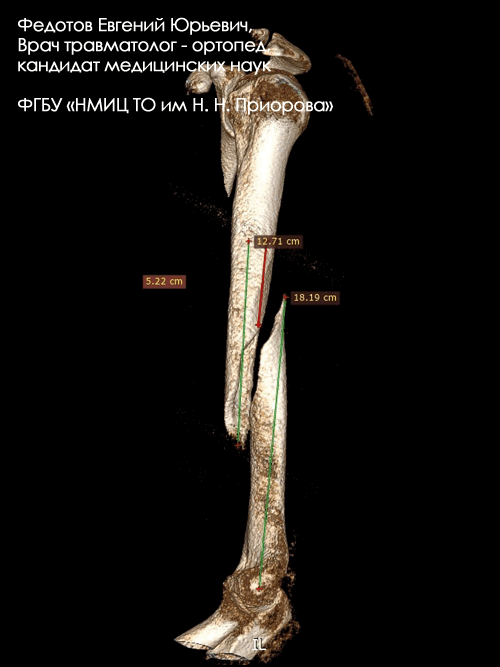

Переломы диафиза плечевой кости

Переломы диафиза плеча, как и все другие, подразделяются на переломы от прямой и непрямой травм. При прямом приложении силы возникают поперечные, оскольчатые и многооскольчатые (в том числе и сегментарные) переломы, а при непрямом — винтообразные (косые) с дополнительным осколком или без него. Одним из типичных вариантов перелома от непрямой травмы являются закрытые винтообразные переломы, полученные во время армрестлинга. В последние годы их число заметно увеличилось, видимо, за счет популяризации этого вида единоборств.

«Золотым стандартом» лечения таких переломов является блокированный интрамедуллярный остеосинтез. Методика позволяет через мини-доступы выполнять репозицию и обеспечивать стабильную фиксацию переломов.

Перелом диафиза плечевой кости

Переломы диафиза плечевой кости составляют примерно 1% от всех переломов. Обычно они являются следствием прямой травмы, но также могут возникать и в тех видах спорта, где велики ротационные силы, например, в бейсболе и армрестлинге. Переломы в/3 плечевой кости могут приводить к повреждению подмышечного нерва. Переломы средней и дистальной трети могут подвергать опасности лучевой нерв.

Остеосинтез пластиной позволяет хирургу выполнить хорошую репозицию и создать стабильную фиксацию компонентов с межфрагментарной компрессий костных отломков. Пластина в таких случаях является наилучшим средством при коррекции деформации и остается методом выбора при лечении ложных суставов плечевой кости.

Другим вариантом лечения переломов диафиза является интрамедуллярный остеосинтез.

Закрытый перелом ср/3-н/3 плечевой кости со смещением.

Операция: открытая репозиция отломков ср/3-н/3 плечевой кости, остеосинтез пластиной и винтами